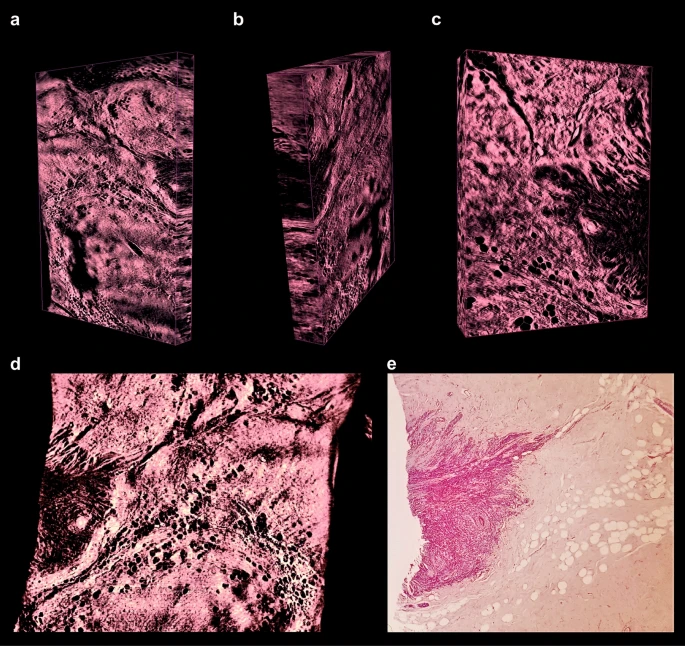

(a)用福尔马林/ 5-磺基水杨酸固定和增强组织自发荧光

(b)用2,2-二甲氧基丙烷进行的超快活性化学脱水

(c)在最高56°C下与二苄基醚匹配的折射率

清除后,对肿瘤切除部位成像。图像经过计算处理后以增强对比度和去除伪影,然后进行3D重建。

预处理后,使用可视化软件AMIRA 6.7(德国Thermofisher)三维重建了600–2,000张图像的堆栈。由于肿瘤记录是单色的,因此必须通过其特征性自发荧光强度来区分不同类型的组织(图 1 d1,e1,f1)。我们发现最高的自发荧光强度对应于红细胞和微钙化,血管结构和胶原纤维。因此,血管结构和胶原纤维用2×或4×放大倍数(图变得可见 1 D2,E2),红细胞(图 1 F 2,4 G)可以使用16×放大率被识别。核(放大16倍)(图 4d,f)和脂肪细胞(放大2倍或4倍)(图2 d,e,3 d)由于自身荧光较低而显得较暗。